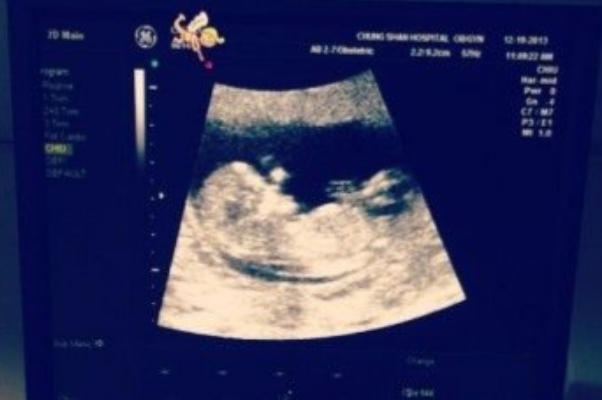

在孕期检查中,B超作为评估胎儿发育状况的重要手段,其检查结果往往牵动着准父母的心。近年来,一种名为“B超位置不好90%是女孩”的说法在民间广泛流传,甚至被部分人奉为“经验之谈”。这一观点声称,当B超检查中胎儿位置不佳、难以清晰观察时,往往预示着胎儿为女孩。然而,这一说法是否具有科学依据?本文将从医学角度出发,结合B超检查原理、胎儿性别影响因素及孕期健康管理等方面,为您揭开这一谣言的真相。

B超检查的准确性受多种因素影响,包括胎儿体位、胎盘位置等。当胎儿位置不佳时,医生可能难以获取清晰的图像,但这并不意味着检查结果不可靠。事实上,B超检查的主要目的是评估胎儿健康,而非预测性别。因此,将B超位置与胎儿性别联系起来,缺乏科学依据,甚至可能误导准父母对胎儿健康的关注。

B超检查在孕期主要用于监测胎儿发育、评估胎盘功能及筛查先天性异常。医生通过观察胎儿头部、四肢、脊柱等结构,判断胎儿是否健康。性别辨别并非B超检查的常规项目,除非在特定情况下(如遗传病筛查),医生才会关注胎儿性别。